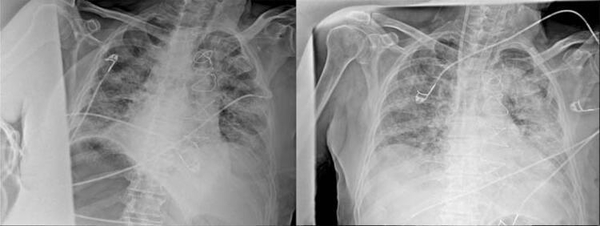

Anadolu Ajansı (AA) Ankara Şehir Hastanesinde Kovid-19 tedavisi gören hastalara ait akciğer görüntülerine ulaştı. Görüntülerde, hastalığın ne kadar hızlı ilerlediği ve akciğerleri nasıl tuttuğu ortaya çıktı.

Prof. Dr. Karalezli, koronavirüs tedavisi gören hastalara ait akciğer görüntülerinden hastalığın yol açtığı tahribatı ve hastalar üzerindeki etkileri anlattı.

Normal akciğer görüntüleri ile koronavirüs hastalarının akciğer görüntüleri arasında ciddi farklar bulunduğunu belirten Karalezli, şu bilgileri verdi:

"İnsanların aradaki farkları anlamaları için her iki akciğer görüntülerine de yer verdim. Görüntülerdeki beyazlıklar akciğerdeki tutulumu gösteren görüntüler ne yazık ki. Bu hastalar yoğun bakım hastaları. Filmler birbirine az çok benzeyen şekilde. Altta yatan hastalığı olanlarda ise daha kötü seyrediyor."

Kliniğe yeni başvuran bir hastanın, 5 Ağustos'ta çekilen tomografi görüntülerindeki tipik koronavirüs görüntülerinin olduğunu ifade eden Karalezli, hastanın bir hafta içerisindeki tomografi görüntüsünde ciddi değişiklik olduğunu ve enfeksiyonun çok arttığını söyledi.